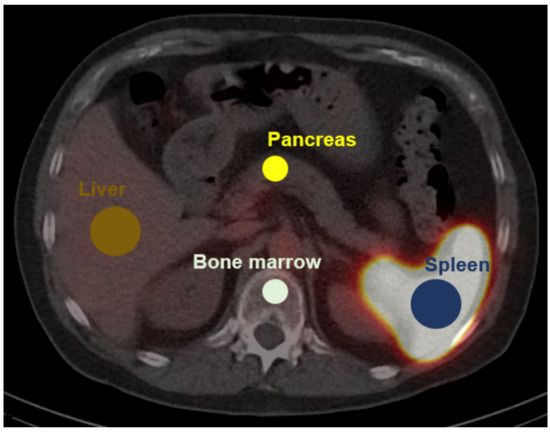

For uptake quantification, hepatic uptake served as reference tissue and was quantified using a spherical 3.0 cm diameter volume-of-interest (VOI) in the non-diseased right hepatic lobe [19]. Uptake in sites of physiologic uptake was quantified using spherical VOIs (diameter 1.5 cm: bone marrow and, if available, pancreas; diameter 3.0 cm: orthotopic spleen [20]). Figure 1 illustrates the VOI definition. For evaluation of suspected splenic tissue, scans were reviewed by 4 nuclear medicine physicians and rated either as vital splenic or non-splenic lesions. The uptake characteristics of the lesions were then quantified using a VOI-based approach consisting of a manually drawn VOI in three adjacent axial layers centered on the maximum uptake of the lesion. Based on uptake quantification in sites of physiologic uptake, a quantitative cutoff for the differentiation of splenic from non-splenic tissue was defined.

Figure 1.

VOI definition for quantification of physiologic uptake. 99mTc-labelled denatured red blood cells single photon emission tomography (SPECT) is fused on low dose computed tomography (CT). Diameter of spherical 3D-VOIs: pancreas 1.5 cm, bone marrow 1.5 cm, spleen 3.0 cm, liver 3.0 cm.